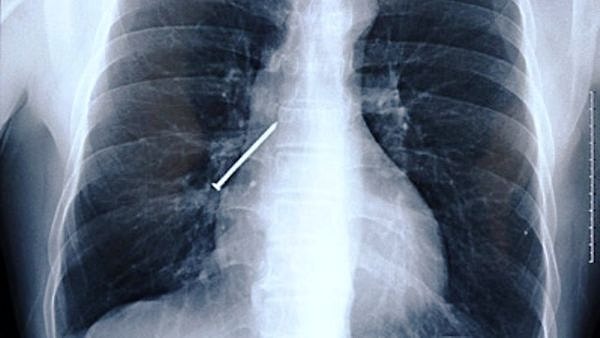

Удивительное рядом: 14 самых неожиданных вещей, найденных у пациентов при рентгене

В общем, ситуации самые разные. А уж предметы и подавно: зажигалки, фонарики, бутылки, гвозди. И даже живые лягушки 🙊